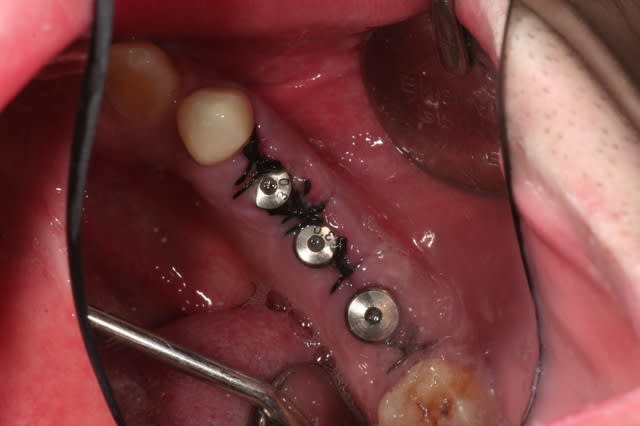

le traitement poursuit son bonhomme de chemin..

une vue du côté droit après élongation coronaire à une semaine...

à suivre..

ce matin, pose de trois implants.